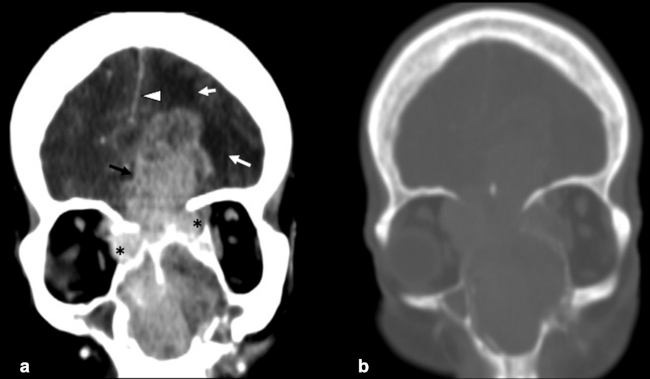

La TC de corte fino (espesor de corte de 1 mm) con reconstrucciones en plano coronal y sagital, es la mejor prueba de imagen inicial para el estudio del NBO. En la TC, aparece como una masa homogénea de tejido blando en la bóveda nasal con realce moderado y uniforme (►Figs.1y2). Se pueden encontrar calcificaciones punteadas dispersas (►Figs.2,3,4,5a,6).50 El valor principal de la TC es una mejor definición de la afectación ósea en comparación con la RM. La TC ayuda a evaluar la erosión ósea de la placa cribiforme, la fóvea etmoidal y la lámina papirácea (►Figs.1,2,3,4,5a,8). Sin embargo, la remodelación ósea sin erosión puede presentarse en algunos casos debido a su patrón de crecimiento indolente.3,35,49 Los estudios de TC generalmente revelan un patrón lítico y muy raramente hiperostosis dominante que simula displasia fibrosa.51 La TC también es útil para evaluar la presencia de metástasis regionales en cuello y a distancia.52,53

La RM es la prueba de imagen de elección para evaluar los detalles de la extensión y la estadificación locorregional del tumor. La RM es superior a la TC para determinar el grado de afectación del tejido blando (►Fig. 9) con una mejor evaluación de la afectación intracraneal (►Figs.10,11,12,13,14), orbital (►Figs.14y15), de la base del cráneo y la invasión perineural.53,54 La RM tiene un valor añadido para distinguir la afectación dural de la del parénquima cerebral (►Fig. 12).55 En la RM, el NBO aparece hipointenso respecto a la sustancia gris en imágenes ponderadas en T1 y de isointenso a hiperintenso en las imágenes ponderadas en T2 (►Figs.10,11,12,13,14,15).56 Muestra un realce homogéneo, excepto en áreas con hemorragia o necrosis. Además, permite diferenciar las secreciones retenidas del tumor, al ser estas hiperintensas ponderadas en T2.53,55 Los hallazgos de imágenes clásicos incluyen una masa “en forma de mancuerna” que se extiende a través de la placa cribiforme (►Fig. 12), con la parte estrecha a nivel de la placa. Los quistes tumorales periféricos (►Figs.5b,12,14,16) y las calcificaciones moteadas son bastante característicos de NBO.1